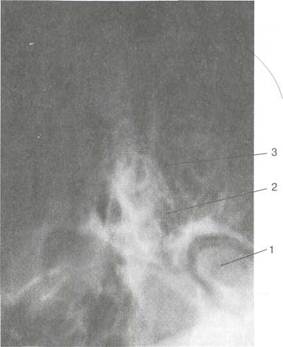

Рис. 1.7. Непрямая ларингоскопия (гипофарин-госкопия).

а — положение гортанного зеркала (вид спереди); б — положение гортанного зеркала (вид сбоку); в — картина гортани при непрямой ларингоскопии: 1 — надгортанник, 2 — ложные голосовые складки, 3 — истинные голосовые складки, 4 — черпало-видный хрящ, 5 — межчерпаловидное пространство, 6 — грушевидный карман, 7 — ямки надгортанника, 8 — корень языка, 9 — черпалонад-гортанная складка, 10 — под-голосовая полость (кольца трахеи).

Картина при непрямой ларингоскопии. 1. В гортанном зеркале видно изображение, которое отличается от истинного тем, что передние отделы гортани в зеркале находятся вверху (они кажутся позади), задние — внизу (кажутся впереди). Правая и левая стороны гортани в зеркале соответствуют действительности — не изменяются (рис. 1.7).

2. В гортанном зеркале прежде всего виден корень языка с

расположенной на нем язычной миндалиной, затем надгортан

ник в виде развернутого лепестка. Слизистая оболочка надгор

танника обычно бледно-розового или слегка желтоватого цве

та. Между надгортанником и корнем языка видны два неболь

ших углубления — ямки надгортанника, ограниченные средин

ной и боковой язычно-надгортанными складками.

3. Во время фонации видны голосовые складки, в норме

они перламутрово-белого цвета. Передние концы складок у

места их отхождения от щитовидного хряща образуют перед

нюю комиссуру.

4. Над голосовыми складками видны вестибулярные склад

ки, они розового цвета, между голосовыми и вестибулярными

складками с каждой стороны имеются углубления — желудоч

ки гортани.

5. Внизу в зеркале видны задние отделы гортани; черпало-

видные хрящи, они имеют розовый цвет, с гладкой поверхнос

тью, представлены двумя бугорками; к голосовым отросткам

этих хрящей прикрепляются задние концы голосовых складок,

между телами хрящей располагается межчерпаловидное про

странство.